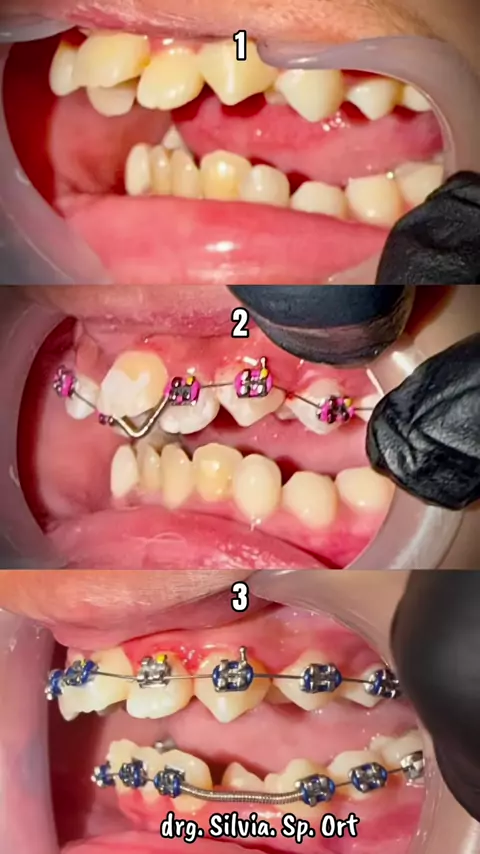

Risk it All... Risk all the cases Brain training Thinking Put it on Move it slowly With my mind and heart Still 3 times Need more but wish not that long Ambil Risiko Semuanya... Ambil risiko semua kasus Latihan otak Berpikir Insersi Gerakkan perlahan Dengan pikiran dan hatiku Masih 3 kali Butuh lebih banyak tapi berharap tidak lama lama I Wish I Pray Good night 🌹 Swet Dream drg. Silvia. Sp. Ort#behel#behelgigi#progress#orthodontist#

HARI INI (Kontrol Ke 4 ) Maloklusi kelas 1, gigi atas dan bawah berdesakan. Pergerakan pelan pelan saja dan semakin indah dalam 5 bulan, tidak terlalu lama. Masih perlu beberapa perawatan, tetapi kemajuannya nyata, perlu menemukan kunci oklusi di bagian posterior kanan. Rotasi gigi dan gigi yang berdesakan telah terkoreksi dengan baik. Alhamdulillah Y Rabb Semua ini karena tuntunanmu semata di pikiran dan hatiku, selama seluruh perawatan dan perjalanan pemasangan behel. Allah Maha Besar, Mah...

The Oclussion Kunci gigitan, kasus boderline, plek ketika digigit dan ditutup tidak ada cekah atas bawah kecuali sisa ruang sedikit untuk retraksi anterior. good night drg. Silvia. Sp. Ort #behelgigi #behelstory #orthodontist #surabaya #

Anterior Retraction with Wire Bending No need powerchain Make any kind of loop of wire bending technique Trying back doing this Boring with powerchain We could do anything with wire bending Need to learn more Need to train more I am not the expert as @Drg Paulus Maulana Sp Orto @Octavin Spesialis Orthodontist @Felix The Orthodontist I am just Bak Pia Pathok At least I am trying my best 🌹🌹 Last Night #orthodontic #orthodontist #surabaya #educatorsof #